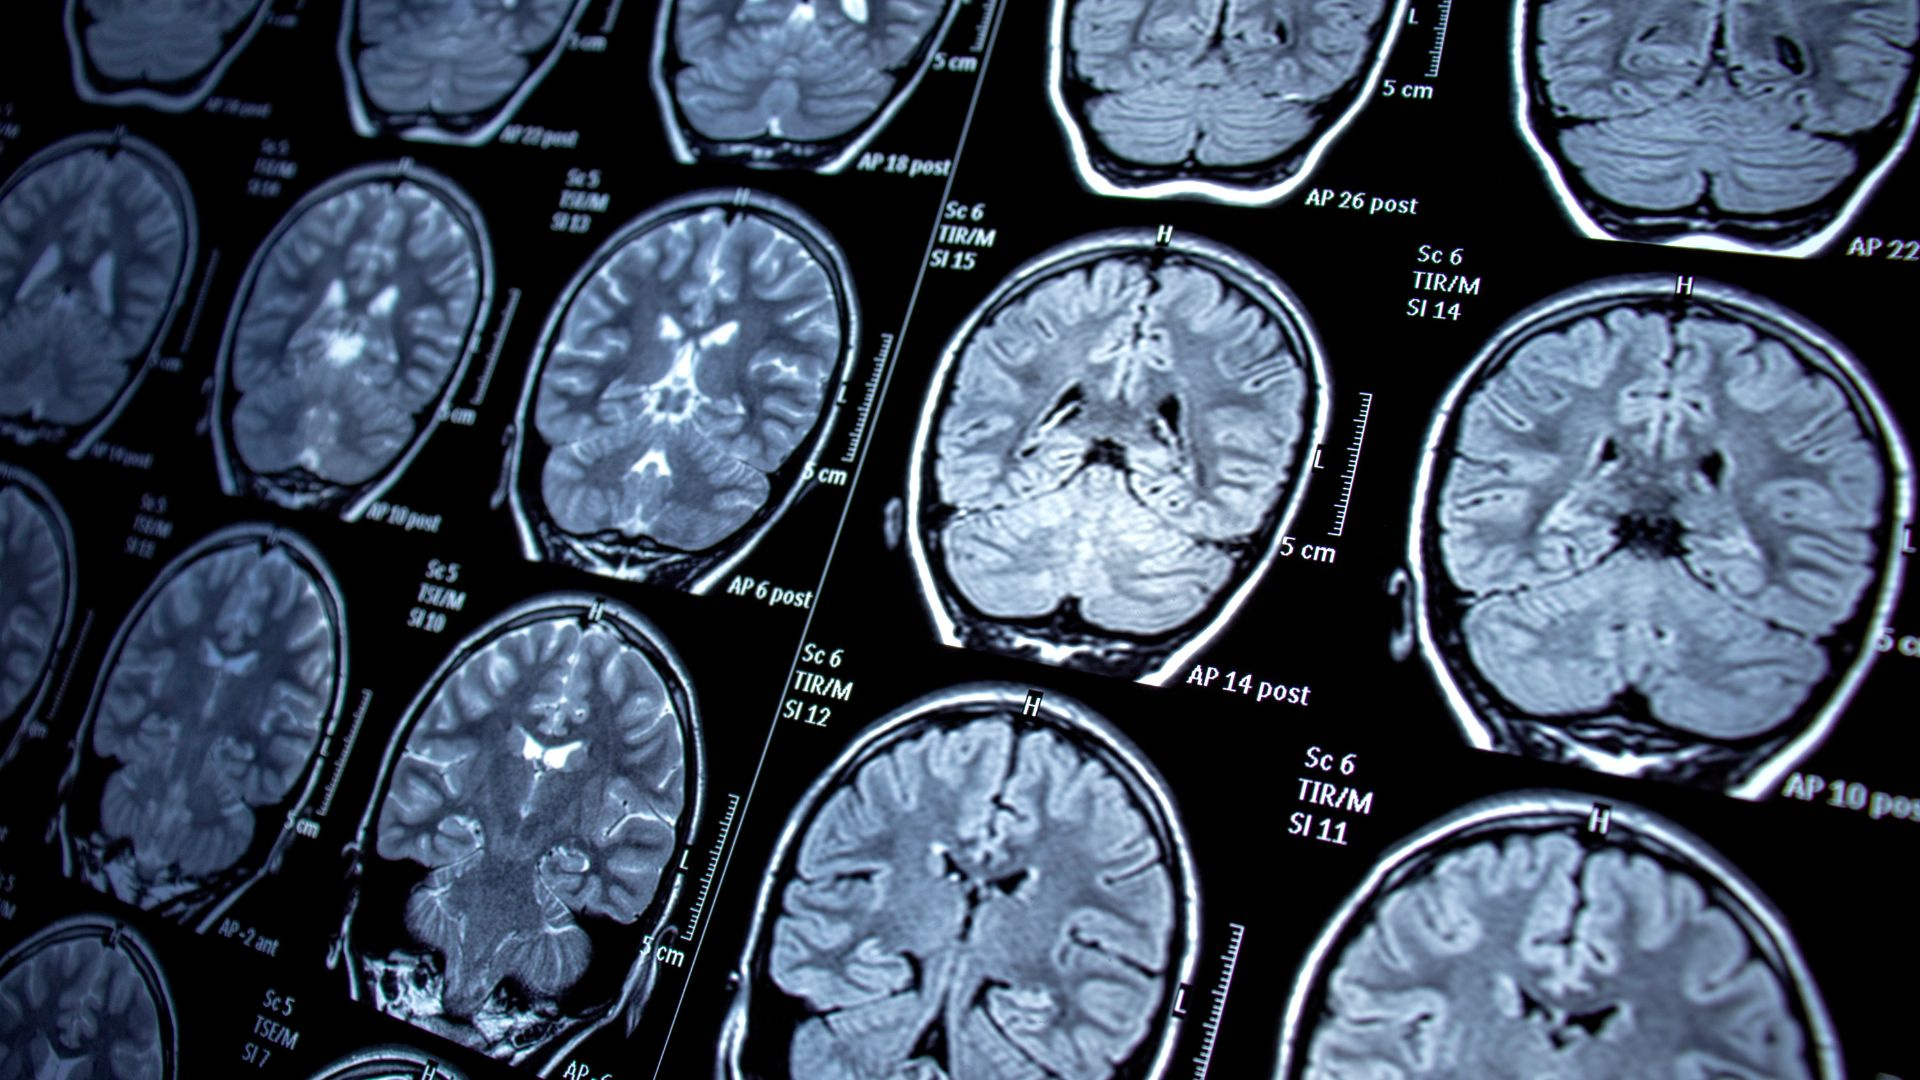

La localidad de Baiona (Pontevedra) ha acogido esta semana un encuentro que ha reunido a destacados epileptólogos y neurólogos del norte de España y Portugal, con el foco puesto en las necesidades aún no cubiertas de las personas que conviven con epilepsia. La reunión, coordinada por la Dra. Xiana Rodríguez Osorio, neuróloga del Complexo Hospitalario Universitario de Santiago de Compostela (CHUS) y especialista en epilepsia, ha servido para actualizar conocimientos y compartir experiencias sobre el manejo de esta enfermedad neurológica. En una entrevista concedida en el marco de las jornadas, la doctora Rodríguez subraya la importancia de escuchar de primera mano a los pacientes y sus familias para mejorar el acceso a una atención integral, tanto médica como emocional y social. QUÉ ES LA EPILEPSIA La epilepsia es un trastorno neurológico crónico caracterizado por crisis epilépticas recurrentes debidas a descargas eléctricas anómalas en el cerebro, que pueden provocar convulsiones, ausencias, alteraciones sensoriales o cambios bruscos de comportamiento. Se trata de una de las enfermedades neurológicas más frecuentes en el mundo, con unos 50 millones de personas afectadas, según la Organización Mundial de la Salud. Puede aparecer a cualquier edad y tener un impacto significativo en la vida laboral, académica, social y emocional de quienes la padecen, lo que hace imprescindible un enfoque que vaya más allá del mero control de las crisis. Los expertos reunidos en Baiona insisten en la necesidad de combinar tratamiento médico, apoyo psicológico y recursos sociales que reduzcan el estigma y favorezcan la autonomía de los pacientes. NUEVOS FÁRMACOS Y TERAPIAS El tratamiento de primera línea sigue siendo la medicación antiepiléptica, cuyo objetivo es reducir la frecuencia e intensidad de las crisis y lograr, cuando es posible, periodos prolongados sin convulsiones. En los últimos años se han incorporado nuevos fármacos, como cenobamato, fenfluramina y cannabidiol de uso farmacológico, que ofrecen alternativas para pacientes con epilepsia farmacorresistente y síndromes como el de Dravet o Lennox-Gastaut. Estos medicamentos han demostrado reducir de forma significativa las crisis en epilepsias de difícil control, mejorando la calidad de vida en casos seleccionados. Junto a los fármacos emergentes, las jornadas de Baiona han puesto el foco en terapias avanzadas como la cirugía de la epilepsia y los sistemas de neuroestimulación, que tratan de modular la actividad eléctrica cerebral mediante dispositivos implantables cuando la enfermedad no responde a los tratamientos habituales. La investigación en terapias génicas y celulares para determinadas epilepsias raras abre, además, la puerta a un manejo más personalizado en los próximos años. ATENCIÓN INTEGRAL Y CALIDAD DE VIDA Tal y como destaca la Dra. Xiana Rodríguez en la entrevista, ningún avance será completo si no se acompaña de equipos multidisciplinares, formación al entorno y medidas específicas contra el estigma. La evidencia apunta a que la calidad de vida de las personas con epilepsia mejora cuando, además del control de las crisis, se garantizan la integración social, la estabilidad psicológica y el apoyo familiar y comunitario. Por ello, los expertos reunidos en Baiona defienden mantener un enfoque integral y centrado en la persona, en el que neurólogos, psicólogos, neuropsicólogos y trabajadores sociales trabajen de forma coordinada para que el diagnóstico de epilepsia no implique renunciar al proyecto de vida de cada paciente.